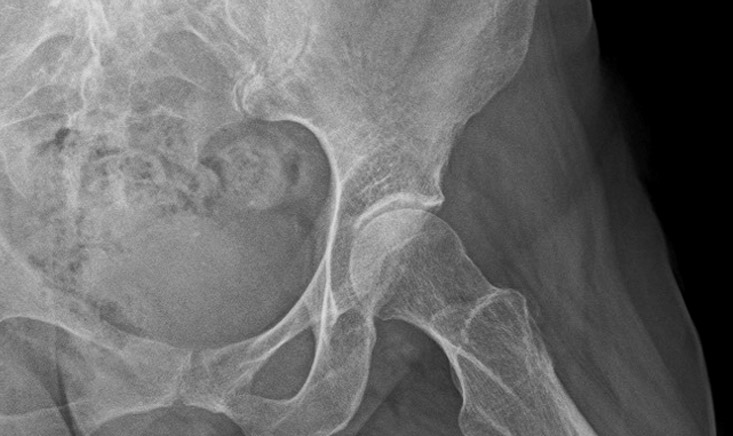

Pre-op X-rays

• Tonnis 1 Hip osteoarthritis ✔️

• Coxa profunda ✔️

• Femoroacetabular impingement Pincer type ✔️

• Anterior hip osteoarthritis ✔️